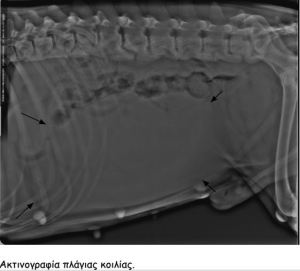

Στον υπέρηχο βρέθηκε ενδοκοιλιακή μάζα η οποία καταλάμβανε

όλη την κοιλιακή κοιλότητα και απωθούσε το λεπτό έντερο

Η μάζα αυτή ήταν ο όρχης ο οποίος είχε παραμείνει στη

κοιλιακή κοιλότητα και είχε εμφανίσει κακοήθη εξαλλαγή.